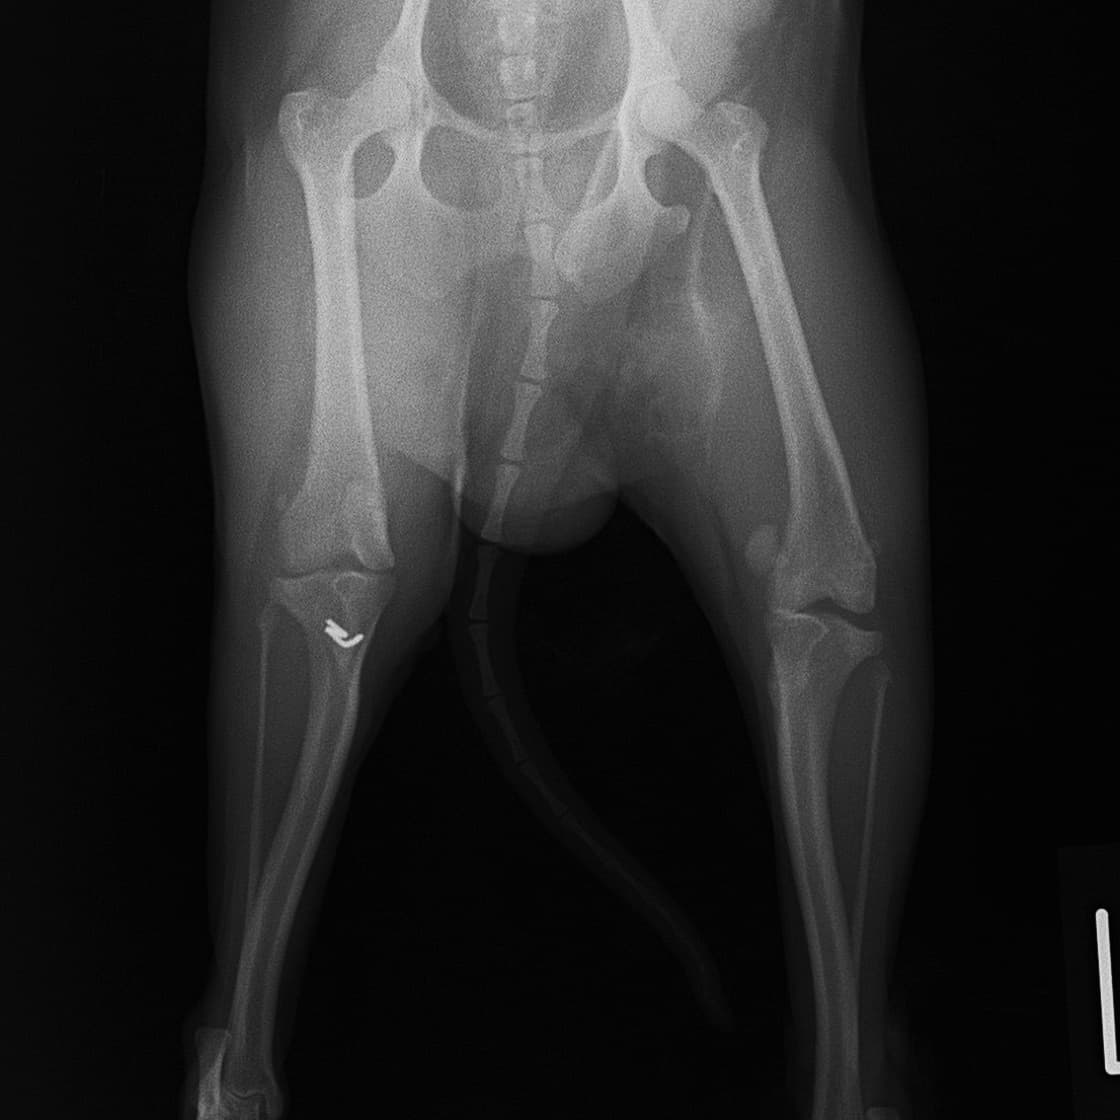

■ 症例24 キャバリア 7か月

左右膝蓋骨内方脱臼(左:グレードⅣ 右:グレードⅢ)

以前から左右後肢の跛行が認められ、整形外科学的検査・レントゲン検査により左右の膝蓋骨脱臼が認められた。症状が重度である左膝の膝蓋骨脱臼整復術を行った。外科手技は縫工筋及び内側広筋の解放、脛骨粗面の外側転位、滑車ブロック形造溝術、内外側関節方の縫縮を実施した。術後一か月時点で、左の膝蓋骨は安定しており経過は良好である。

本症例は成長期における重度の膝蓋骨脱臼であり、術後の再発の可能性もあるため、経過をしっかりと観察していく必要がある。また、今回手術を実施していない右膝に関しても経過を観察し、手術を検討していくこととする。